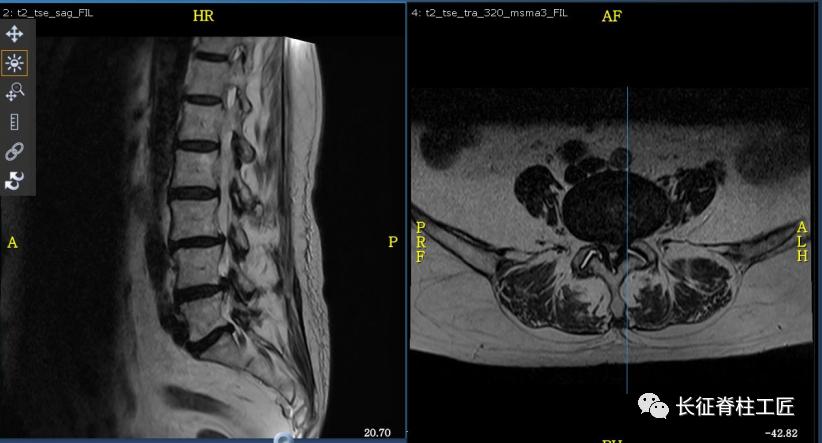

入院检查,腰部疼痛,后伸时加剧,局部压痛,双下肢肌力减退。X线检查,L4、L5骨质增生,MRI显示L4/L5、L5/S1椎间盘突出,马尾神经受压明显,被确诊为腰椎管狭窄症。

马尾神经是脊髓和周围神经的桥梁,脊髓的末端一般位于第2腰椎水平(腰椎共5节),脊髓末端就接着马尾神经,第2腰椎以下的腰椎管狭窄或腰椎间盘突出,压迫马尾神经,就会产生马尾神经综合征。

马尾神经综合征早期表现为会阴部麻木、感觉减退。当出现大小便功能障碍时,提示神经功能已经严重损害,应该立即采取急诊减压手术治疗,解除对马尾神经的压迫,尽可能挽救马尾神经功能。